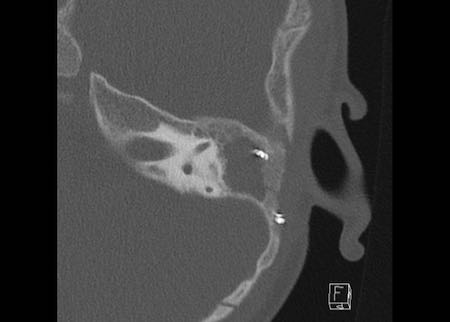

Bên trái là hình ảnh của một bệnh nhân có xương bàn đạp nhân tạo.

Xương bàn đạp nhân tạo bằng kim loại bị lạc chỗ và nằm trong tiền đình.

Bệnh nhân được phẫu thuật lại và đặt xương bàn đạp nhân tạo mới.

Lưu ý vùng giảm tỷ trọng nhỏ tại fissula ante fenestram, dấu hiệu của xơ cứng tai (mũi tên).